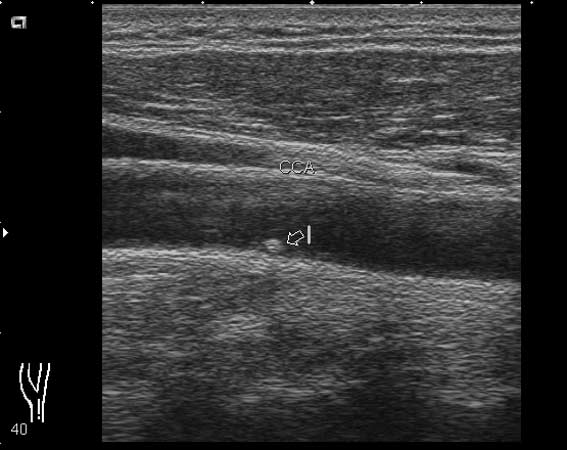

мужчина, 49 лет, при обследовании БЦА в общей сонной артерии визуализируется округлое образование 1.7х2.0 мм

Общая сонная артерия

Кальцинированная атеросклеротическая бляшка. Для уточнения ее истинного размера примените энергетический доплер.

локальная атеросклеротическая бяшка, которая не вызовет гемодинамически значимых изменений(если оценивать бляшку только в продольном сечении)